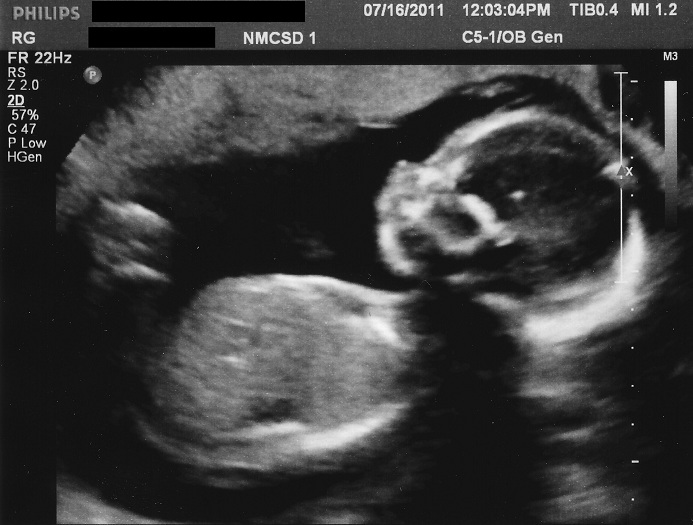

And his profile shot from 21 weeks:

Attachment 16695